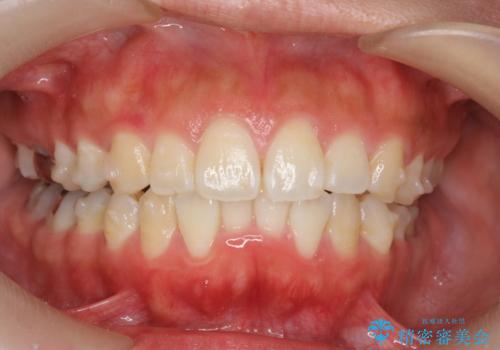

前歯の角度を改善するマウスピース矯正

- 前歯の角度・重なりの改善を求めて矯正治療を希望され来院されました。

通常このような場合、小臼歯を4本抜去しワイヤー矯正を行う治療計画も検討されますが、今回は側方に拡大できる骨量が十分に存在したため抜歯をしない矯正治療の計画を立てます。

しっかりと拡大を行い、IPRも併用したことで歯並びと前歯の角度を大幅に改善することができました。